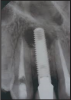

Digital Radiology

Digital imaging was introduced into dentistry in 1987. Digital sensors are used instead of film receptors. Sensors can be wired or wireless depending on the system used (Figure 78). Sensors and tube head placement are the same for digital imaging as film and tube head placement is for traditional radiology. Most standard radiographic machines can be converted to acquire digital images. Digital imaging still uses ionizing radiation, and until recently it was believed that before any digital radiographic images are exposed, the patient must be draped with a protective apron and thyroid collar. The National Council on Radiation Protection & Measurement (NCRP) published new guidelines for the use of protective aprons and digital imaging. The new guidelines state that if an office only uses digital solid-state image receptors, protective aprons are only required when the patient is pregnant or could be pregnant. Protective thyroid collars are mandatory on pediatric patients. These protective devices should be placed on the patient in a way that will not interfere with the image.

The sensors are slightly thicker than a regular receptor. Modified receptor holding devices must be utilized in the placement of the sensors. These modified holders can be purchased from any major dental supply company. The sensors can be reused many times. Proper use of intraoral barrier and OSHA infection control techniques must be observed.